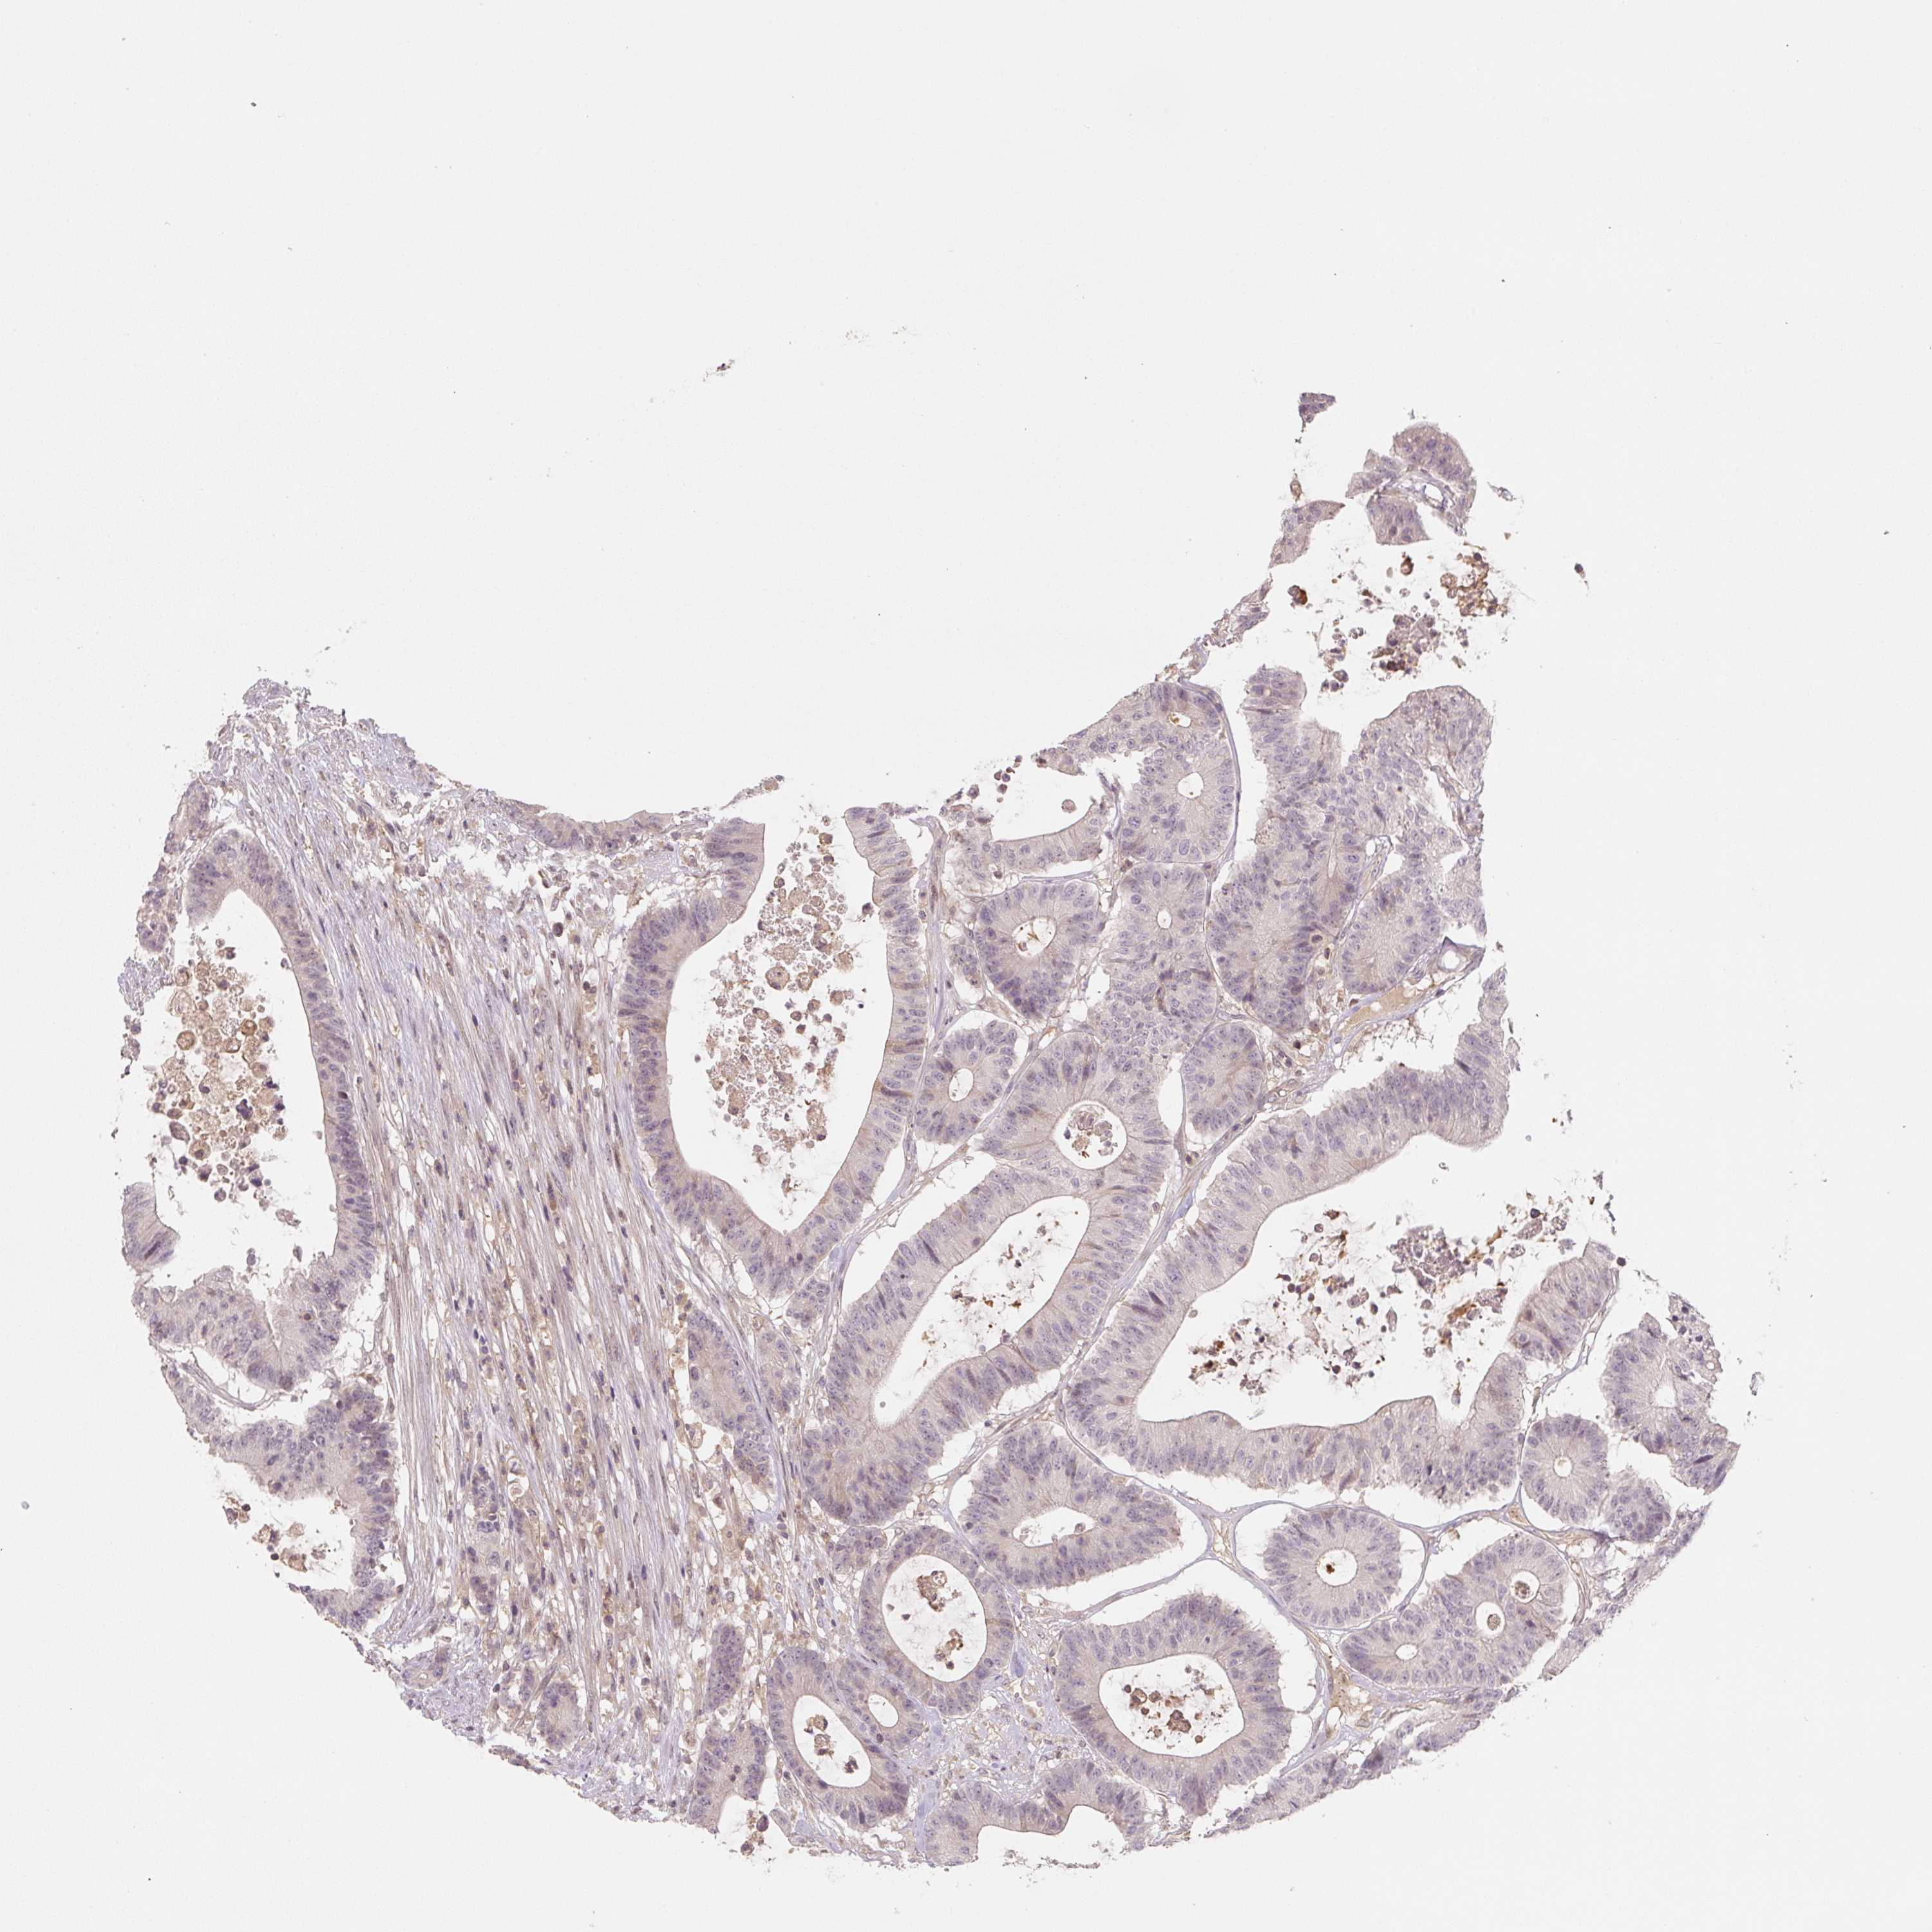

Colorectal cancer

Rectum adenocarcinoma